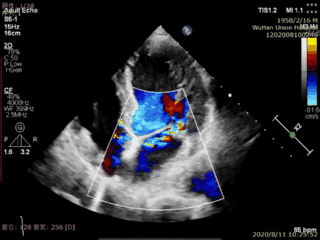

The patient in this case was an elderly male with multiple comorbidities. Preoperative echocardiography showed prolapse and flail of the posterior mitral leaflet (P2) accompanied by severe mitral regurgitation. The surgery was performed under transesophageal echocardiographic guidance, with the implantation of one Type IIIs mitral valve clip. Immediately after the surgery, mitral regurgitation disappeared, and the catheter operation time was less than 20 minutes, resulting in the successful completion of the surgery.

Preoperative echocardiogram